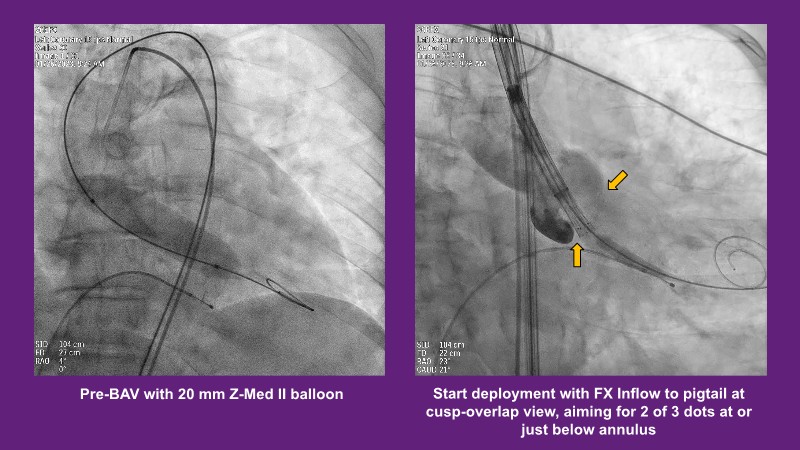

Don’t miss this PCR Tokyo Valves 2025 session replay, where leading experts share key techniques for simplifying and optimising TAVI procedures with the Evolut device. This session covers essential insights into safely performing procedures on patients with various anatomical types using the self-expandable valve, while emphasising the importance of long-term patient care and outcomes. Discover valuable strategies for surgical explantation of transcatheter aortic bioprostheses, coronary cannulation, and commissural alignment post-TAVR. Learn expert tips for streamlining procedures, such as semi-rapid pacing, using Dryseal long, and skipping pre-BAV to improve TAVI results. Watch now to stay ahead in the field!

- To understand simple procedure as semi-rapid pacing, using Dryseal long and skip pre-BAV